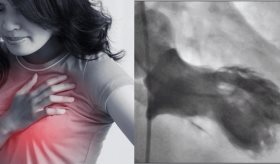

Luego de nueve años de hacer parte de la Sociedad Puertorriqueña de Cardiología, el Dr. Luis Renta es el nuevo presidente de la sociedad.